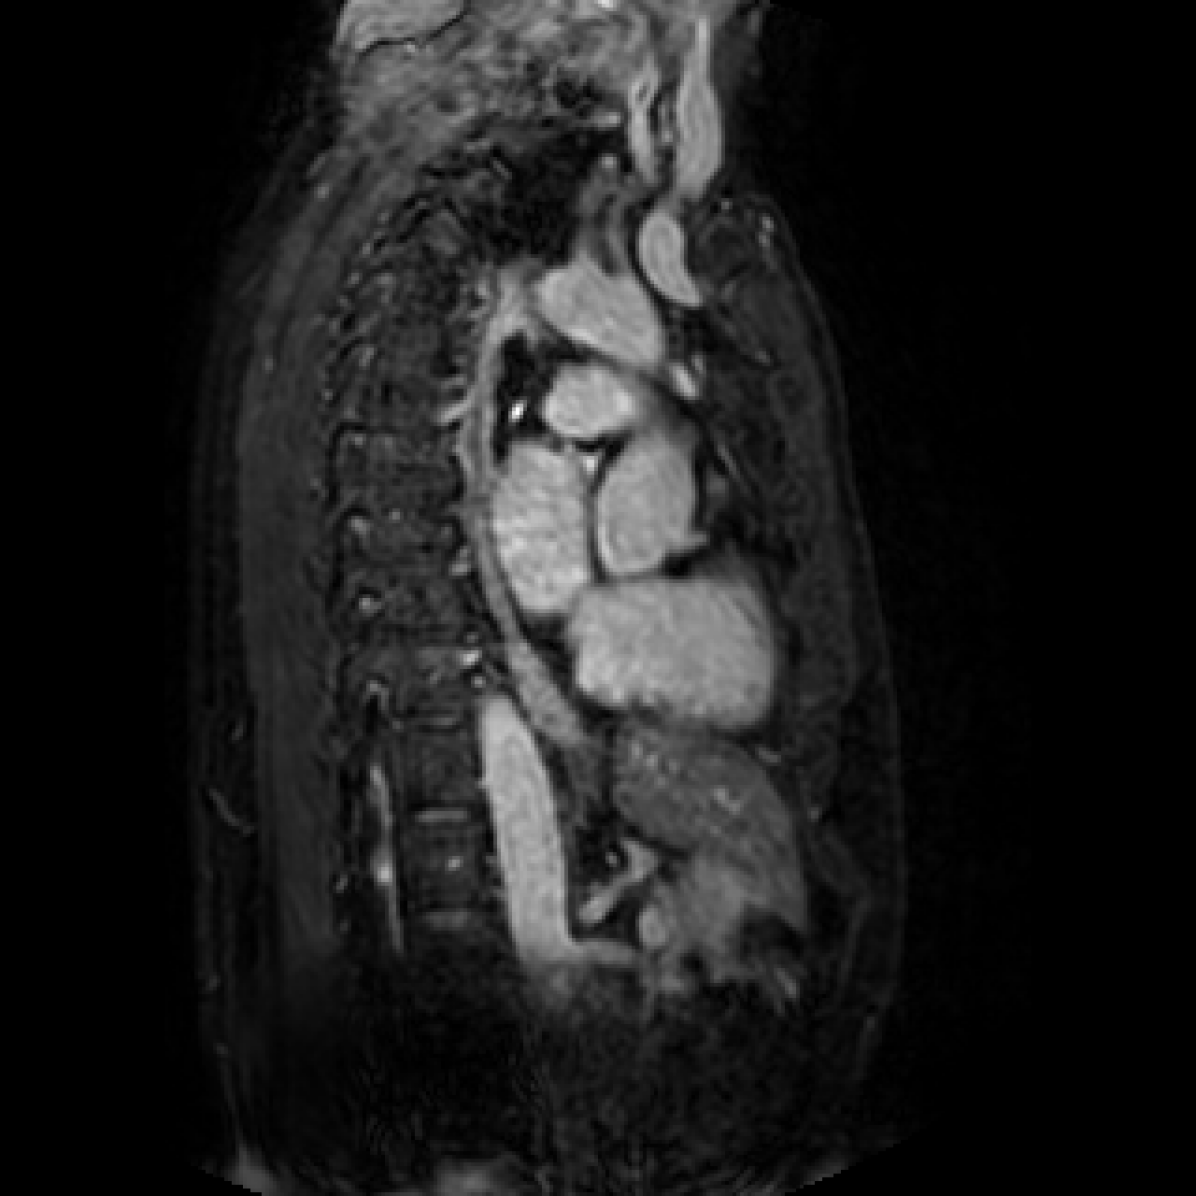

In this section we will show qualitative results of DINOv2 features using principal component analysis (PCA) performed on DINOv2 patch features on X-ray, CT, and MRI scans, following the method delineated in [8]. We will also provide organ segmentation results of linear compared U-Net decoders.

PCA visualization. Figure 2 shows the first three PCA components. The PCA is computed between patches of images that are in the same column, and the first 3 components are shown for X-ray, CT, and MRI scans. Thresholding is used on the first PCA component to remove the background. Just like in natural images [8], the colors of the three PCA components correspond well with the same parts of images in the same category. This is an easier task however, compared to natural images, because there is less variability between examinations on medical images compared to natural images.